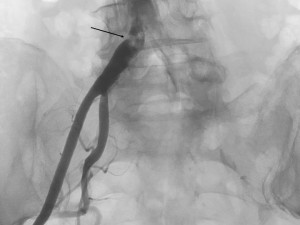

The arterial approach was right femoral, with a 6F introducer sheath. The angiography confirmed the presence of a sub-occlusive stenosis in the right common iliac artery (Figure 1), with important calcification of the terminal aorta and of both common iliac arteries. 5000 IU of unfractioned heparin were given intravenousely. After the passage of a hydrophilic wire through the lesion into the abdominal aorta, a pre-dilatation was made, with a 6 mm diameter balloon. After that we implanted an Express LD stent, 8 mm diameter, 37 mm long and performed a post-dilatation with a 9 mm diameter balloon. The final result was good (Figure 2).

Figure 1. Sub-occlusive stenosis of the right common iliac artery; note the intense calcification of the terminal aorta and both iliac arteries.